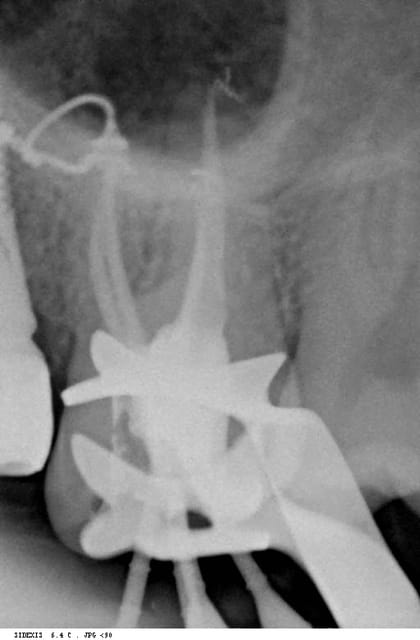

alhoun

19/02/2007 à 18h48

tonio Ecrivait:

-------------------------------------------------------

>

> joli MV2 sur la 26!!!

mais non, c'est une perf, demande à annie.

Perforation ddgr6g - Eugenol

024 vownvo - Eugenol